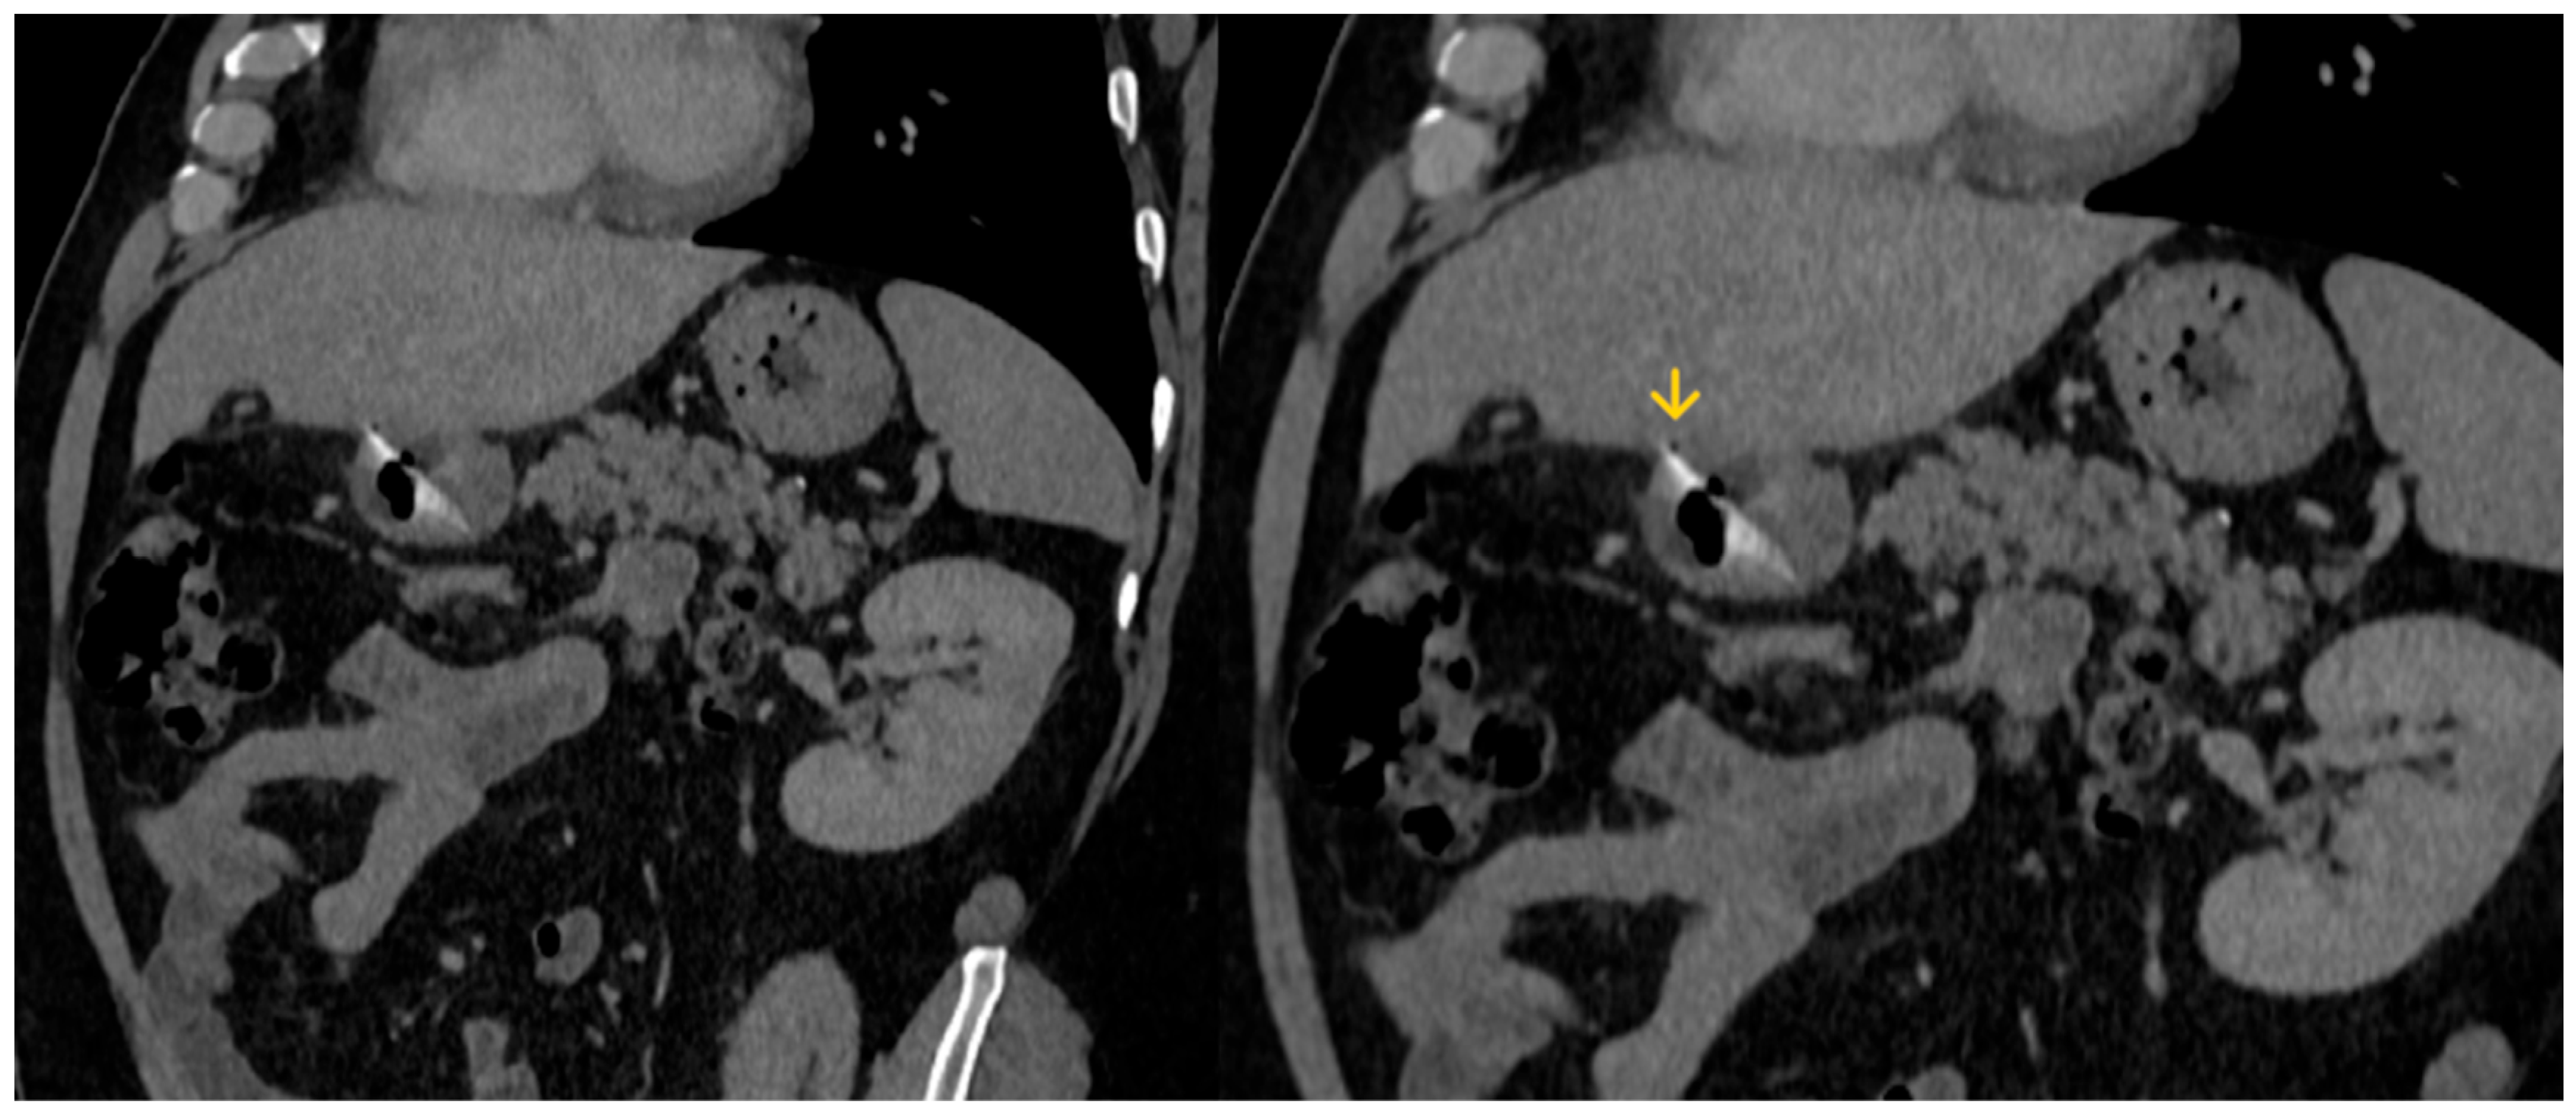

The abdominal CT scan showed a foreign body in the pylorus of the stomach that was penetrating the wall of the stomach (Figure 1). There was also air outside the stomach, along with signs of inflammation in the adjacent adipose fatty tissue (Figure 2 and Figure 3). The diagnosis of perforation of the stomach wall with a foreign body was made, leading to subsequent concealed, local peritonitis.

Figure 2. A linear foreign body is present in the stomach lumen (red arrow), perforating the gastric wall, with surrounding fat stranding (green arrow) resulting from inflammation.

Figure 3. A small amount of gas (yellow arrow) is depicted outside the stomach wall, due to perforation.